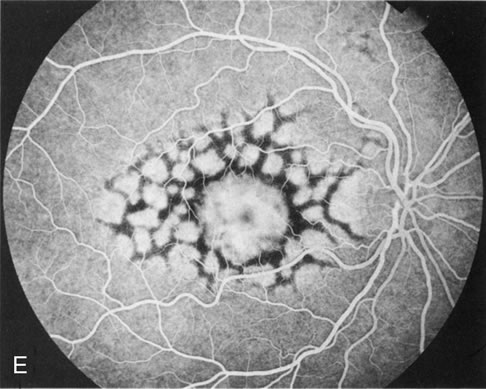

Of more clinical importance is the role of FA in the diagnosis and treatment of cystoid macular edema (CME) (Fig. 1C and D). Stereoscopic FA indicates that the leakage, which may be diffuse or have the typical petaloid stellate appearance of CME, can come from the perifoveal retinal capillaries, from the choroid through the RPE, or from a combination of both sources.4 With the recent suggestion that CME in RP may be successfully treated with acetazolamide,5, 6 FA is thus important to document the diagnosis of CME, establish the origin(s) of leakage, and follow patients during and after therapy.